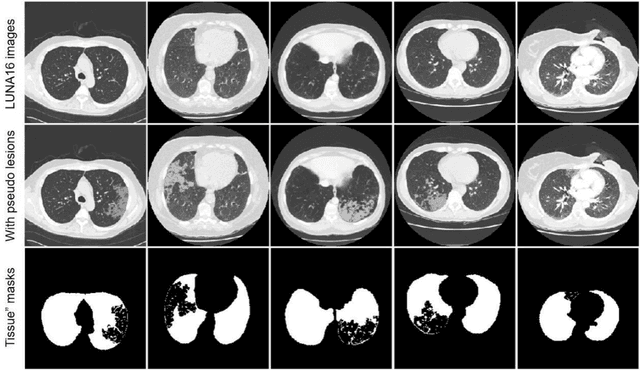

Abstract:Background: Triage of patients is important to control the pandemic of coronavirus disease 2019 (COVID-19), especially during the peak of the pandemic when clinical resources become extremely limited. Purpose: To develop a method that automatically segments and quantifies lung and pneumonia lesions with synthetic chest CT and assess disease severity in COVID-19 patients. Materials and Methods: In this study, we incorporated data augmentation to generate synthetic chest CT images using public available datasets (285 datasets from "Lung Nodule Analysis 2016"). The synthetic images and masks were used to train a 2D U-net neural network and tested on 203 COVID-19 datasets to generate lung and lesion segmentations. Disease severity scores (DL: damage load; DS: damage score) were calculated based on the segmentations. Correlations between DL/DS and clinical lab tests were evaluated using Pearson's method. A p-value < 0.05 was considered as statistical significant. Results: Automatic lung and lesion segmentations were compared with manual annotations. For lung segmentation, the median values of dice similarity coefficient, Jaccard index and average surface distance, were 98.56%, 97.15% and 0.49 mm, respectively. The same metrics for lesion segmentation were 76.95%, 62.54% and 2.36 mm, respectively. Significant (p << 0.05) correlations were found between DL/DS and percentage lymphocytes tests, with r-values of -0.561 and -0.501, respectively. Conclusion: An AI system that based on thoracic radiographic and data augmentation was proposed to segment lung and lesions in COVID-19 patients. Correlations between imaging findings and clinical lab tests suggested the value of this system as a potential tool to assess disease severity of COVID-19.